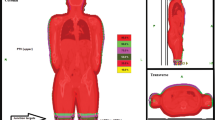

The matching of CT scans and all delineations and planning were performed using an Eclipse Treatment Planning unit (Varian Medical System, Palo Alto, CA, USA). To calculate the optimal dose for irradiating the junctional area, two treatment plans were fused and matched, with JT5 being the lowest part of the upper treatment plan and JT6 being the highest part of the lower treatment plan. The connecting area (JT4–7) was planned with 50% of the prescribed dose. Contouring of the whole body and organs at risk as well as generation of the planning target volume (PTV), sparing the lungs, were performed according to current institutional and international standards [18]. Nine patients underwent treatment planning and delivery using a helical approach (Fig. 1), and 10 patients underwent treatment planning and delivery using a static approach (Fig. 2). Both approaches used fixed jaws, a field width of 5 cm, a pitch of 0.4, and a constant feed rate fitting the pitch and prescribed dose. The modulation factors were 1.6 for the static approach and 2 for the helical approach. With the static approach, the dose was delivered from four angles, all covering the entire PTV. Treatment and planning times were equivalent between the two approaches.

To evaluate the performance of the static approach using a four-field box method compared with the usual helical approach and in consideration of TBI guidelines, we divided the JT volume between the upper and lower CT scans into ten 1-cm-thick volumes (JT1-JT10) covering the entire PTV, spanning from 5 cm above to 5 cm below the marker on the patient’s thigh (Fig. 4). This additional contouring was performed after the completion of treatment for all patients. The dose-volume histogram and the D5, D50, D95, D98, and Dmean as well as the homogeneity index (HI) of each JT and all ten JT volumes combined (JTtotal) were calculated. The HI was calculated using the formula proposed by Kataria et al. (HI = D5/D95) [19].